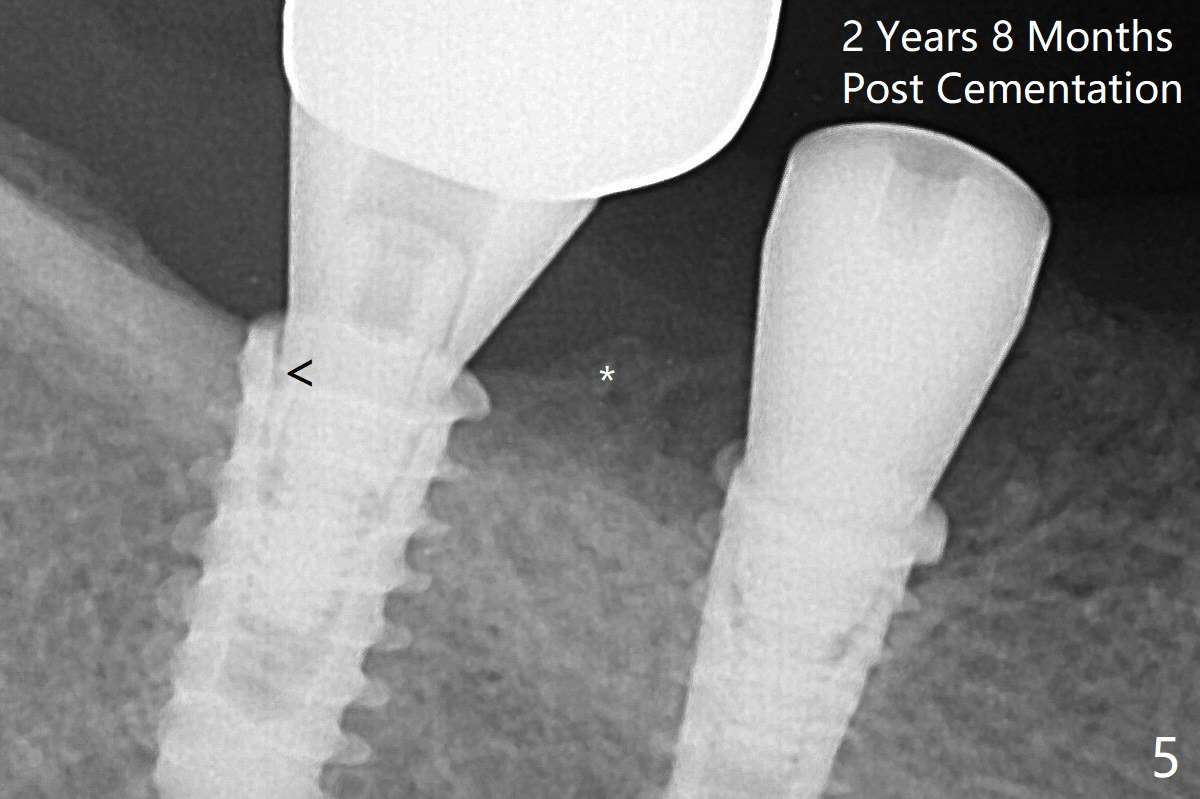

Note bone growth, especially at #30, 2.5 and 4 months postop (Fig.3,4). In fact the abutments are incompletely seated. The crown of #30 is loose with foul smell 2 years 8 months post cementation. It is painful to reinsert the crown/abutment after proximal reduction. A healing abutment is placed (Fig.5). When the incompletely seated abutment at #31 is removed, there is also smell. After separation from the crown, the abutment of #31 returns to the site with change in insertion position, while a smaller abutment has to be used at #30 (Fig.6) due to use of the small healing abutment earlier (Fig.5). A good piece of news is the presence of the bone between the implants (Fig.5,6 *), which contributes to interimplant papilla.